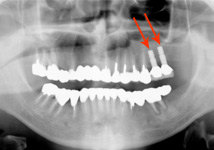

| 長年放置していたために、噛みにくい状態が続き食事がしにくかったところを、左上の奥と右上の奥にインプラントを入れて噛めるようになりました。今ではよく噛めると喜んでいらっしゃいます。 |

|